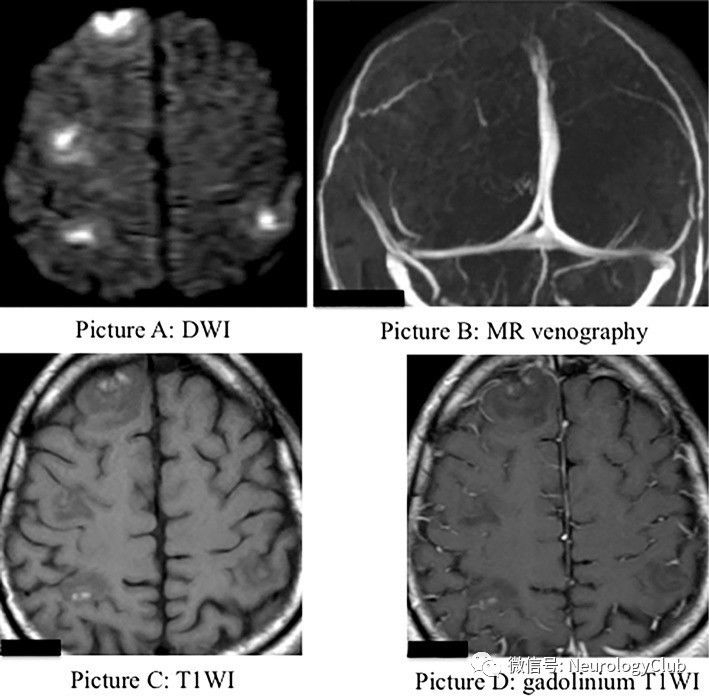

(图14:A:DWI;B:MRV;C:T1WI;D:增强T1WI;多发出血性皮质病变伴强化,MR静脉成像正常)